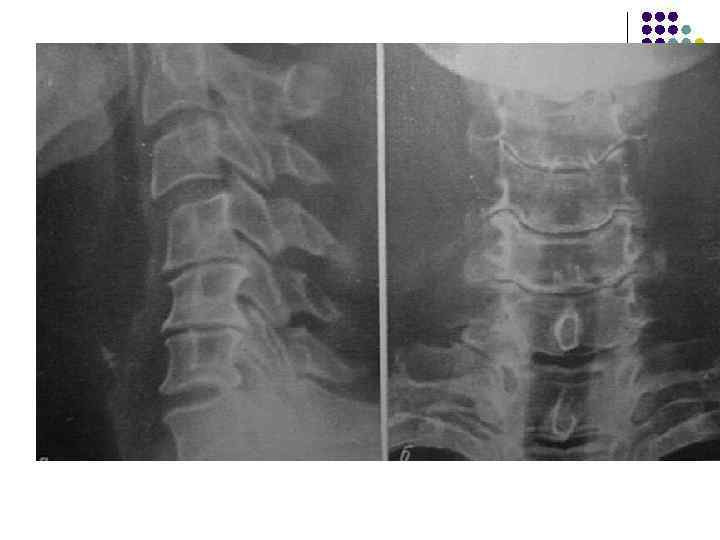

l l l На рентгенограмме шейного отдела позвоночного столба в боковой проекции определяется: выраженные распространенные дистрофические изменения в виде остеохондроза и артроза дугоотростчатых суставов: неравномерное сужение межпозвонковых пространств, субхондральный остеосклероз, костные разрастания по краям тел позвонков, сужение рентгеновских суставных щелей дугоотостчатых суставов с субхондральным остеосклерозом и небольшими костными разрастаниями по краям суставных поверхностей. Наиболее ярко эти изменения выражены в сегментах С 5 -6 -7 Признаки ограниченного смещения тел позвонков в виде симптома «распорки» и кифотической установки. Заключение: Остеохондроз шейного отдела позвоночного столба. Артроз дугоотростчатых суставов. Деформация шейного отдела позвоночника с нарушением статики.

1.

l l l На рентгенограмме шейного отдела позвоночного столба в боковой проекции определяется: выраженные дистрофические изменения за счет остеохондроза - значительное, неравномерное сужение межпозвонковых пространств с нарушением их правильной клиновидной формы, выраженный субхондральный остеосклероз, значительные костные разрастания по передним краям тел позвонков. Наиболее ярко эти изменения представлены в сегментах С-5, 6, 7. Помимо этого, в этих же сегментах фиксируются дистрофические изменения дугоотростчатых суставов – сужение рентгеновских суставных щелей, субхондральный остеосклероз и костные разрастания по краям суставных поверхностей. Выпрямление физиологического лордоза. Признаки системного нарушения статики тел позвонков в виде симптомов кифотической установки. Деструктивных изменений нет Заключение: Комплекс дистрофических изменений шейного отдела позвоночного столба в виде остеохондроза и артроза дугоотростчатых суставов с преимущественными проявлениями в нижних сегментах отдела. Нарушение статики тел позвонков

3.

l На рентгенограмме шейного отдела позвоночного столба в боковой проекции определяется: выраженные дистрофические изменения за счет остеохондроза с преимущественными проявлениями в сегменте С 5 -6 – сужение и деформация межпозвонковых пространств, выраженный субхондральный остеосклероз, значительные костные разрастания по краям тел позвонков. Выпрямление физиологического лордоза. Признаки нарушения положения тела С 4 (симптом «распорки» )

l На рентгенограммах шейного отдела позвоночного столба в двух проекциях определяется комплекс выраженных дистрофических изменений с преимущественными проявлениями в сегментах С 5 -6 -7 в виде остеохондроза и выраженного спондилоза за счет неравномерного сужения межпозвонковых пространств, субхондрального отсеосклероза и костных разрастаний как по краям тел позвонков с продолжением плоскости замыкательной площадки, так и под передней продольной связкой с образованием мощного костного соединения. Положение тел позвонков правильное, деструктивных изменений нет.